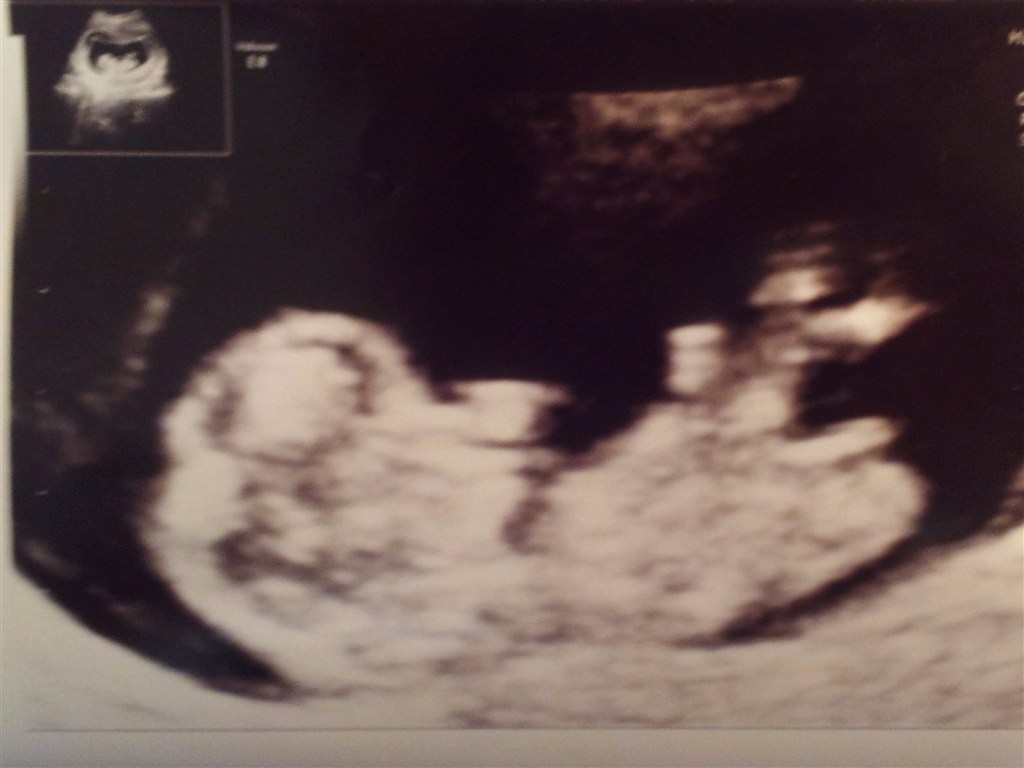

Så har vi været til tryghedsscanning

Og alt gik bare SÅ godt!

Vi så den lille ligge og hoppe, og hørte hjertelyden. Åhh hvor var den fin

Jeg troede jeg ville være ca. 9 uger henne, så da jordemoderen sagde at jeg var 10+5 Blev jeg da helt paf!

Åhh jeg glæder mig til at se den lille igen om et par uger